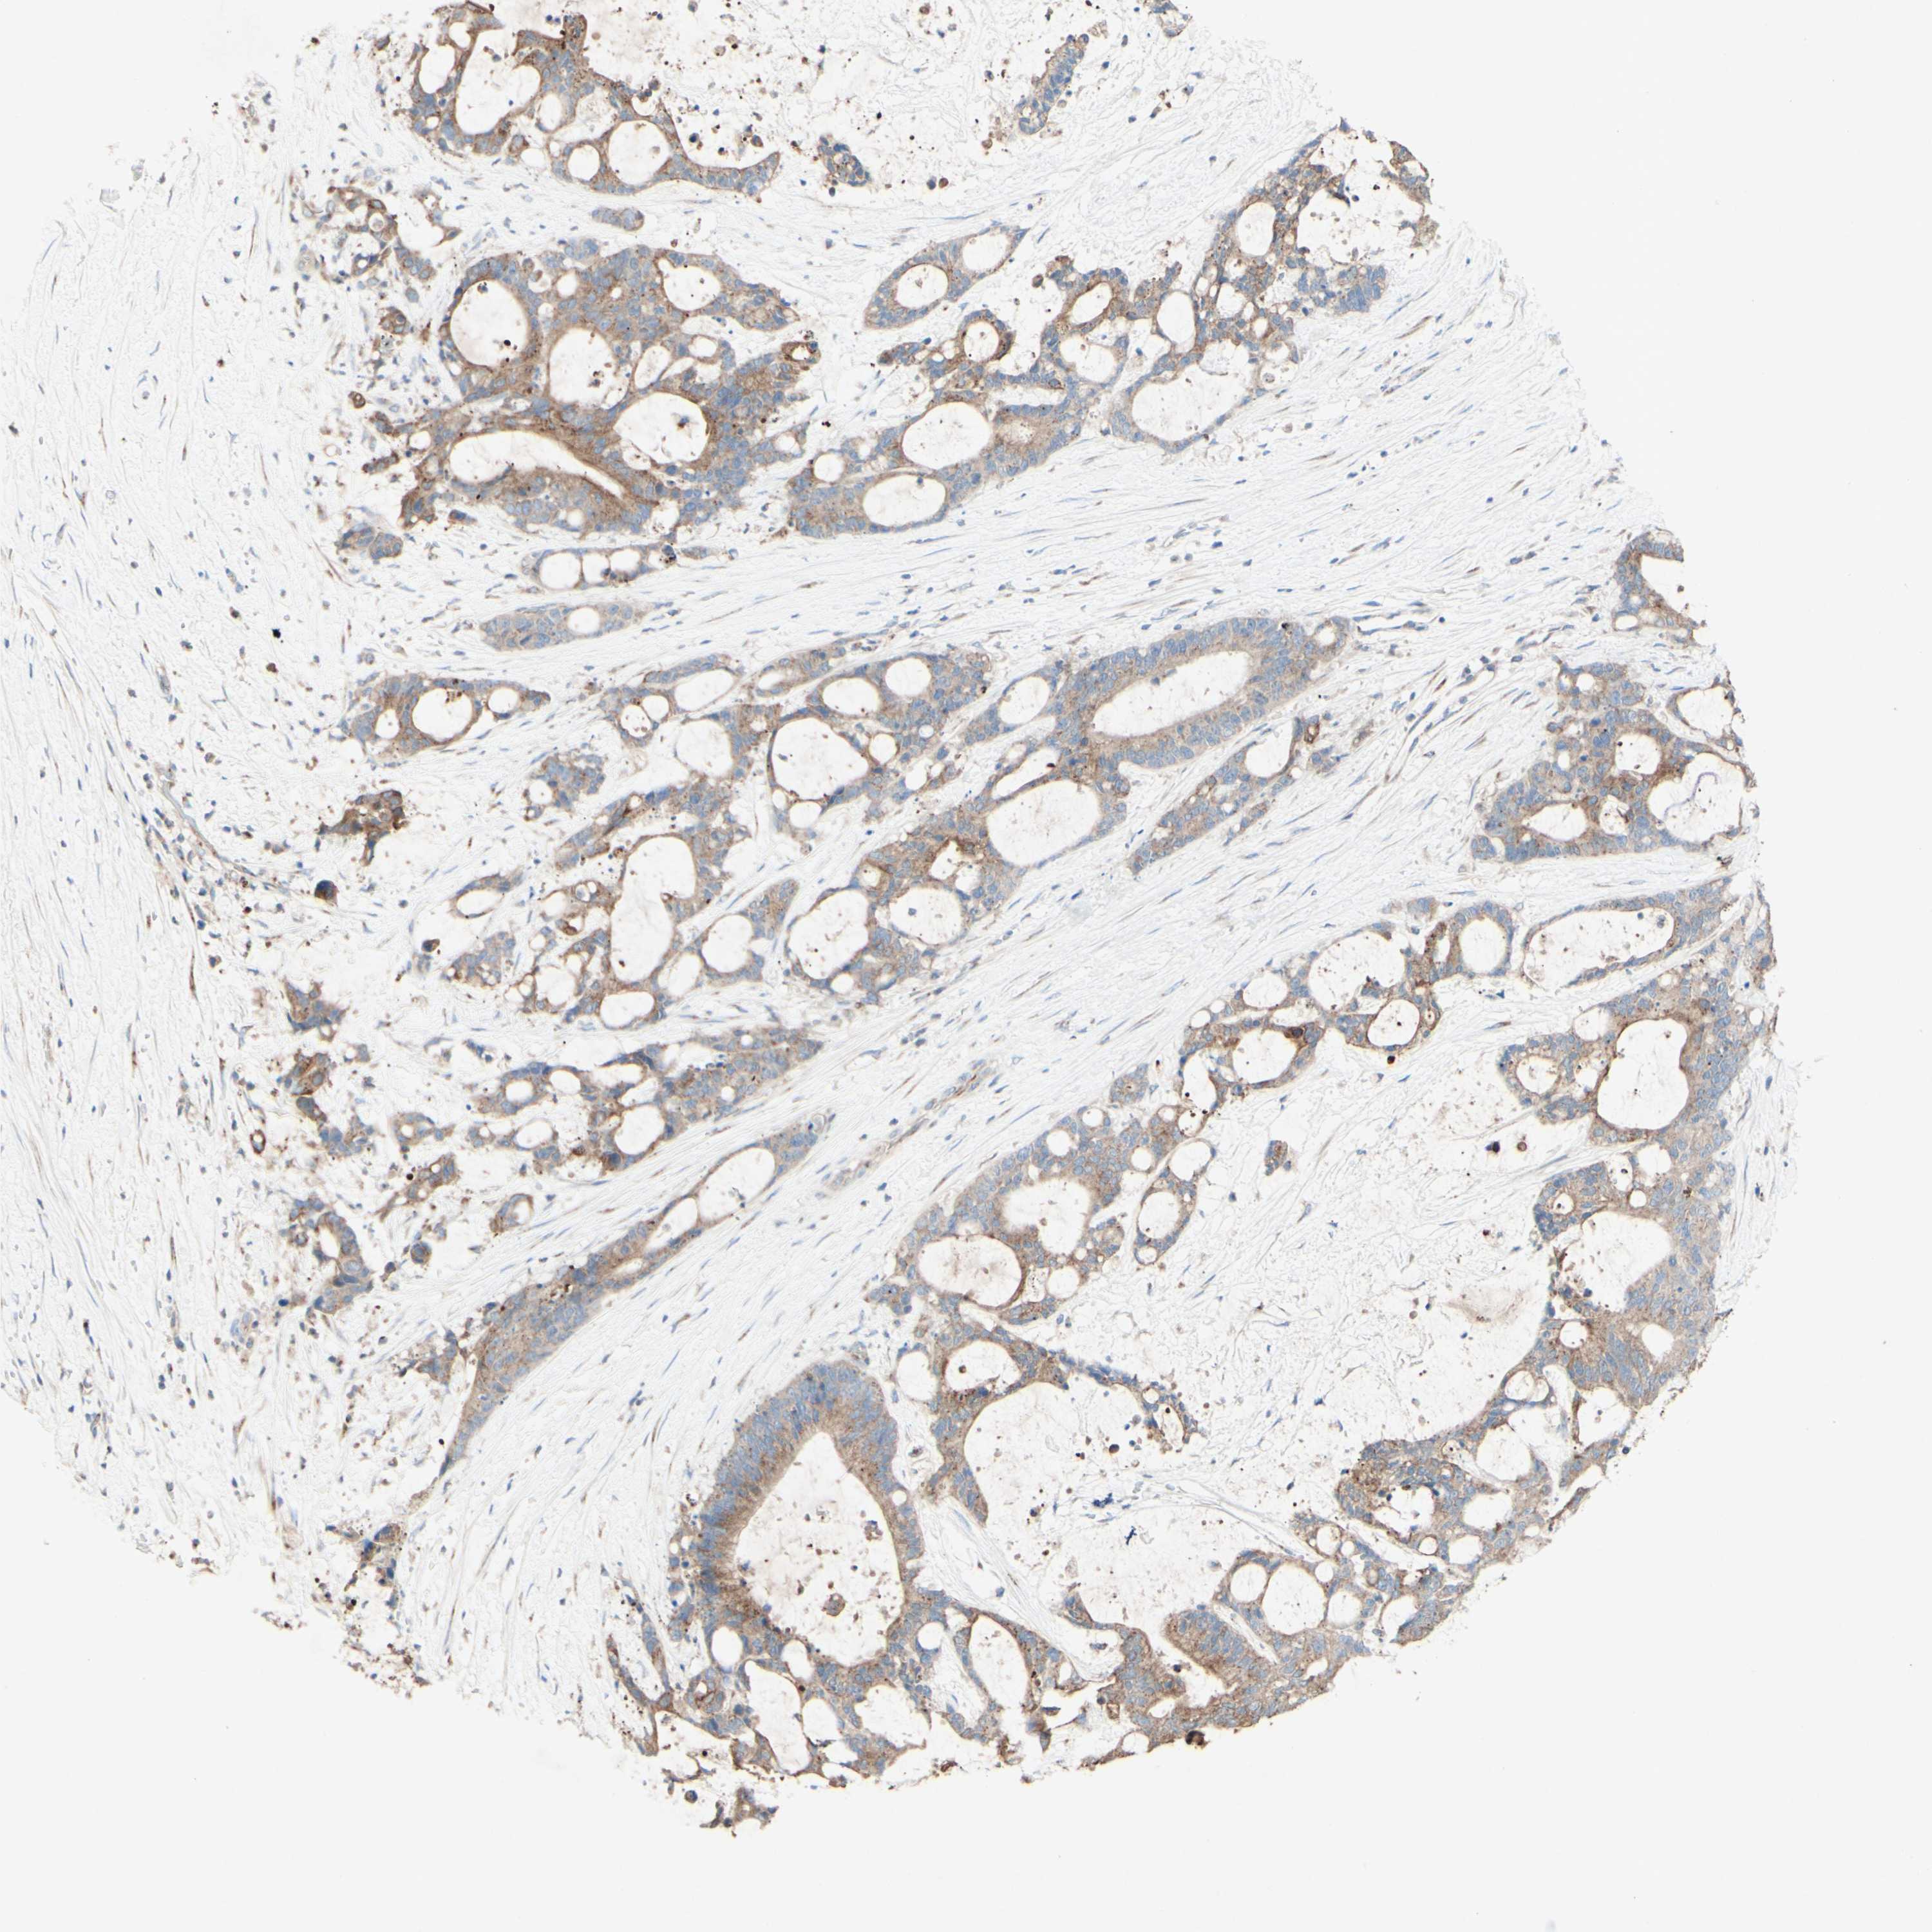

LIVER CANCER - Protein expressioni

A mouse-over function shows sample information and annotation data. Click on an image to view it in a full screen mode. Samples can be filtered based on level of antibody staining by selecting one or several of the following categories: high, medium, low and not detected. The assay and annotation is described here.

Antibody stainingi

Antibody staining in the annotated cell types in the current human tissue is reported as not detected, low, medium, or high, based on conventional immunohistochemistry profiling in selected tissues. This score is based on the combination of the staining intensity and fraction of stained cells.

Each image is clickable and will lead to virtual microscopy that enables deeper exploration of all samples and also displays staining intensity scores, fraction scores and subcellular localization as well as patient and tissue information for each sample.

Antibody HPA010008

Antibody HPA010665

Staining

High

Medium

Low

Not detected

Intensity

Strong

Moderate

Weak

Negative

Quantity

>75%

75%-25%

<25%

None

Location

Nuclear

Cytoplasmic/membranous

Cytoplasmic/membranous,nuclear

Cholangiocarcinoma

Carcinoma, Hepatocellular, NOS